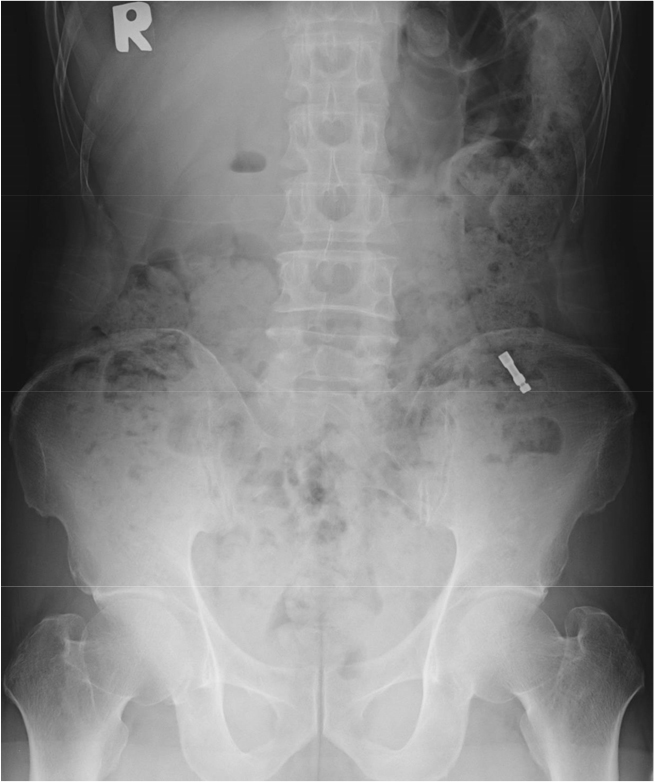

On the day of the surgery, the patient underwent implant placement in the left lower posterior area under local anesthesia. Following the implant placement, location and depth control were conducted with mount extension (ϕ4.8 × 20.5 mm) and a torque wrench. Prevention of swallowing of foreign bodies, including gauze screening, was not performed. During adjustment of the implant location and depth, the patient accidentally swallowed a mount extension into the oropharynx. Despite an immediate attempt to spit out the mount extension, the patient still swallowed it. The patient’s vital signs were stable, and there were no symptoms of discomfort. However, foreign bodies in the airways can cause severe complications. If a mount extension was in his airway, it was removed immediately. The surgical procedure was immediately stopped. Chest posteroanterior (PA) and anteroposterior (AP) radiographs (erect view) were acquired. On two radiographs taken on the day of the swallowing accident, a foreign body was observed in the gastrointestinal tract (Fig. 3). Based on the two radiographs, the foreign body was confirmed to be in the gastrointestinal tract. Because the patient showed no symptoms and the foreign body was expected to be excreted naturally with a low possibility of gastrointestinal perforation, periodic follow-up was performed to confirm that the foreign body was excreted.

Mount extension was observed in a different position in the gastrointestinal tract one week later (Fig. 4). No abnormal signs or symptoms were observed. In general, ingested food is excreted in feces within 24 hours through the gastrointestinal tract. In short, one week may be sufficient for excretion through the gastrointestinal tract. However, the patient answered that he went to the toilet twice a week. Because foreign bodies can cause complications if they remain in the gastrointestinal tract for a long time, the attending surgeon explained the patient’s need to transfer to the Department of Internal Medicine for removal evaluation. However, the patient did not visit an internal medicine doctor for personal reasons. Two weeks after swallowing, the patient came to the clinic, and the mount extension was demonstrated to have been excreted completely on an abdominal AP radiograph (erect view; Fig. 5). No abnormal clinical signs or symptoms were observed.